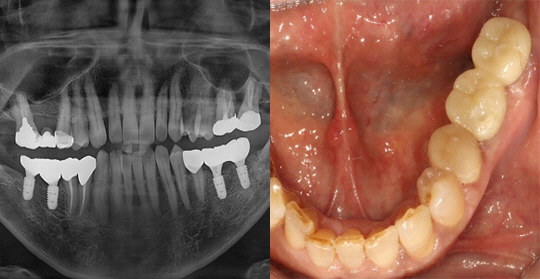

(38세 남 환자)